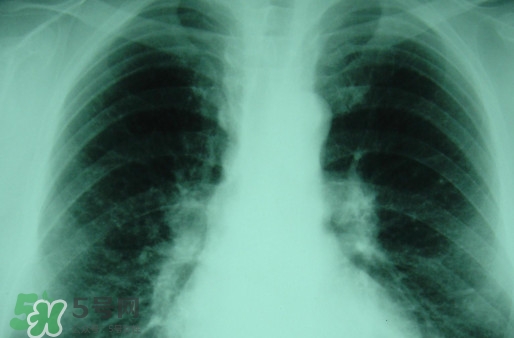

塵肺病多半是肺部灰塵太多導(dǎo)致肺部承載大清理工作降低導(dǎo)致的,對此有人提出換肺治療的方法。那么,塵肺病能換肺治愈嗎?塵肺病不能吃什么?